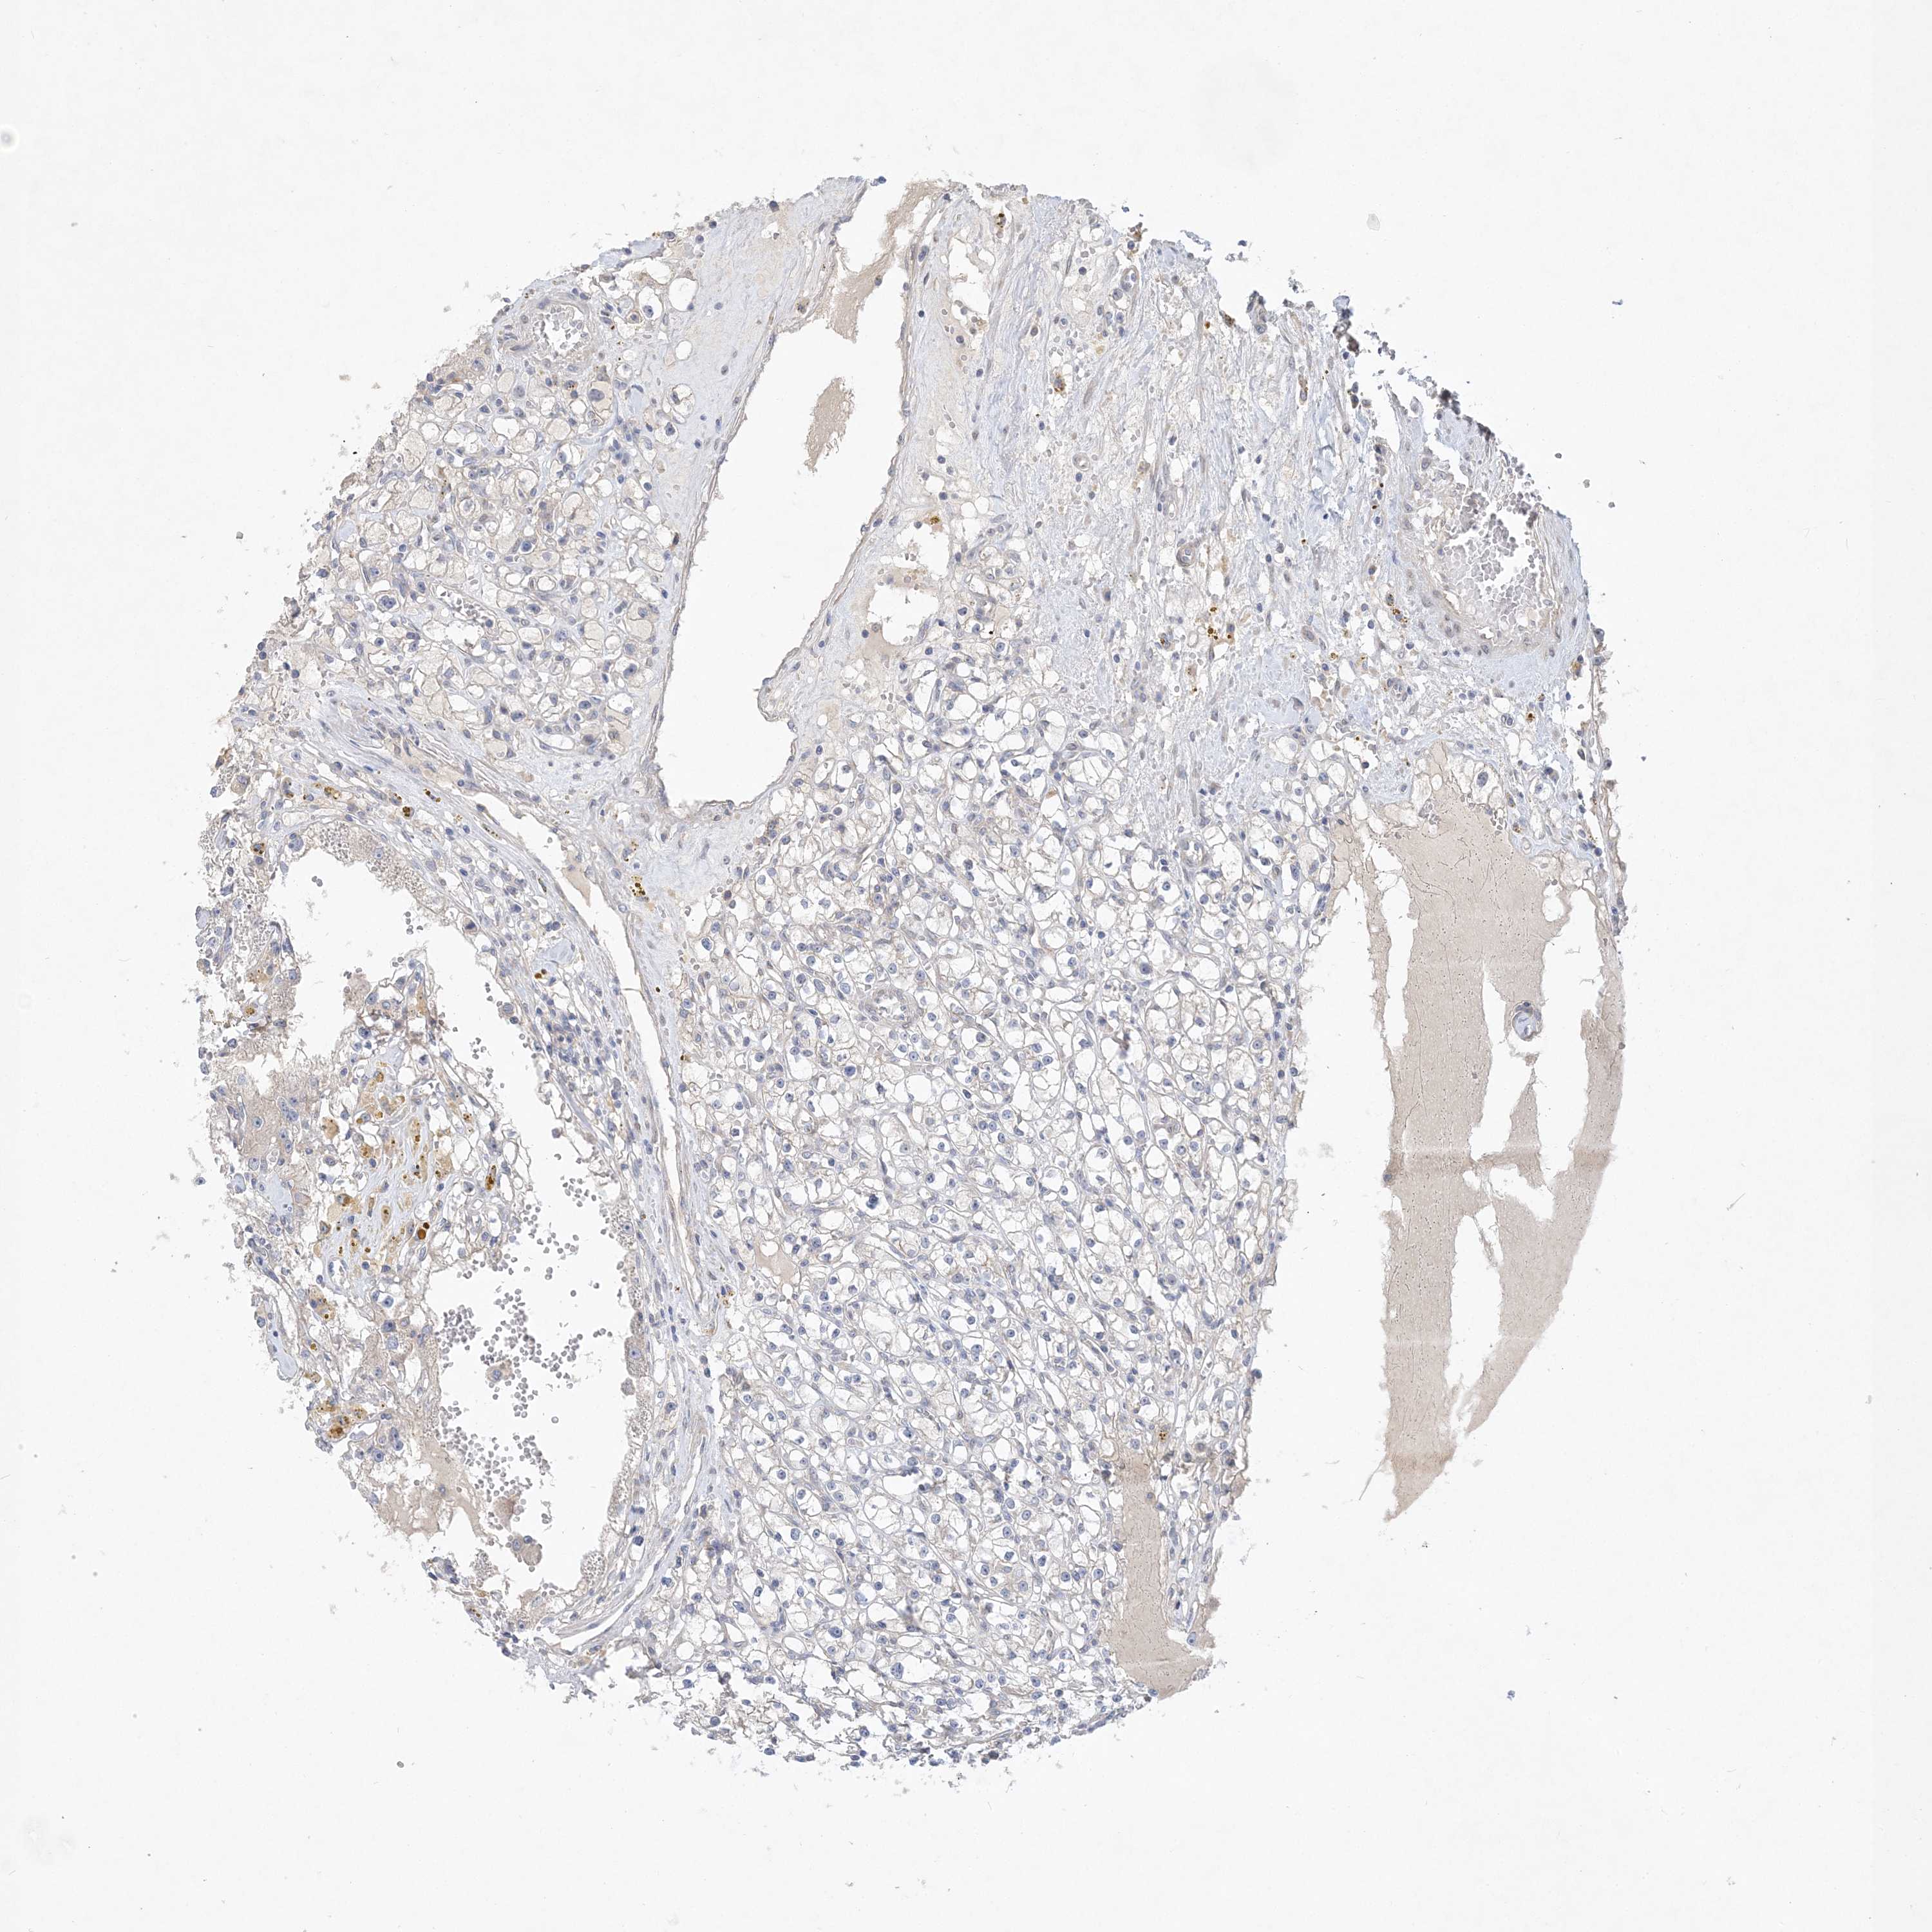

KIDNEY RENAL PAPILLARY CELL CARCINOMA (TCGA) - Interactive survival scatter ploti

The Survival Scatter plot shows the clinical status (i.e. dead or alive) for all individuals in the patient cohort, based on the same data that underlies the corresponding Kaplan-Meier plots. Patients that are alive at last time for follow-up are shown in blue and patients who have died during the study are shown in red.

& Survival analysisi

Kaplan-Meier plots summarize results from analysis of correlation between mRNA expression level and patient survival. Patients were divided based on level of expression into one of the two groups "low" (under cut off) or "high" (over cut off). X-axis shows time for survival (years) and y-axis shows the probability of survival, where 1.0 corresponds to 100 percent.

ANKRD35 is not prognostic in Kidney Renal Papillary Cell Carcinoma (TCGA)